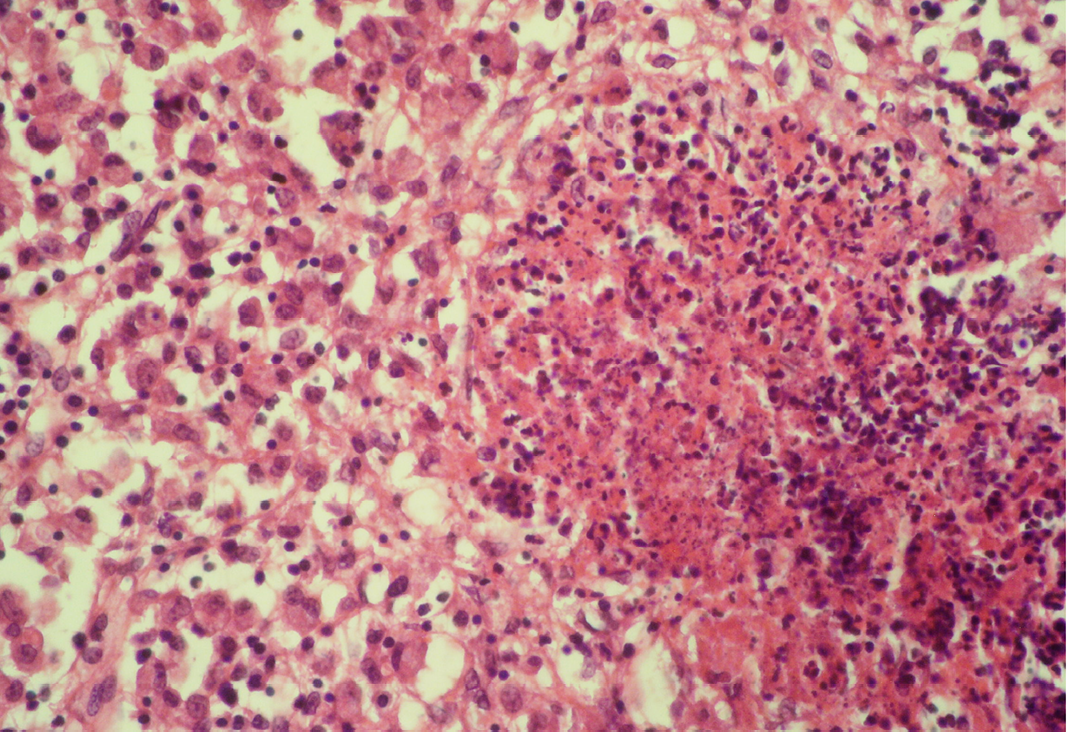

Necrosis of cortical area characterized by karyolysis and karyorrhexis

The area is surrounded by macrophages (histiocytes); H&E x400